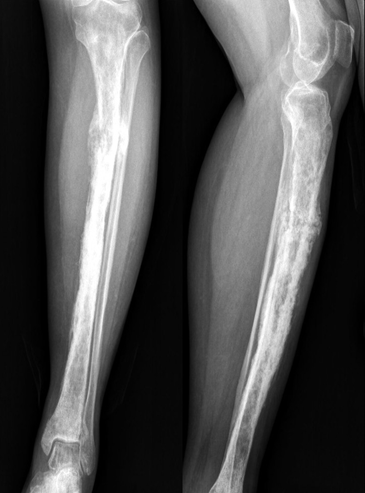

Once the diagnosis of extranodal B-cell non-Hodgkin’s lymphoma involving the left proximal tibia was confirmed–along with regional lymph node involvement–the disease was classified as Ann Arbor Stage IIE. The interval from presentation to histological confirmation was approximately 3 weeks, and chemotherapy was initiated within 1 week of diagnosis. The patient was started on standard R-CHOP chemotherapy (rituximab, cyclophosphamide, doxorubicin, vincristine, and prednisolone), administered every 4 weeks. She has completed four cycles of chemotherapy over the past 4 months and has tolerated treatment well without major adverse effects. Clinically, she reports marked improvement in pain and reduction in swelling, with progressive recovery of mobility. Follow-up radiographs obtained after 4 months demonstrate interval sclerosis and partial cortical remodeling of the previously lytic proximal tibial lesion, with no new cortical destruction or soft-tissue extension, indicating a favorable response to treatment (Fig. 6).

Figure 6: Follow-up anteroposterior (a) and lateral (b) radiographs of the left proximal tibia obtained after four cycles of R-CHOP chemotherapy, showing diffuse homogeneous sclerosis and partial cortical remodeling at the site of the previous lytic lesion. No new cortical destruction or soft-tissue extension is seen, indicating a favourable therapeutic response and interval bone healing.

Given the persistent cortical irregularity and risk of fracture, surgical fixation has been deferred. The patient continues on protected weight-bearing and remains under close orthopedic and oncologic supervision.

After four cycles of R-CHOP chemotherapy over 4 months, the patient showed marked clinical improvement with resolution of pain and swelling. She is now ambulant with a cane and performing daily activities independently. Follow-up radiographs show early sclerosis and bone healing at the previous lytic site, with no new cortical destruction or progression. She continues physiotherapy and oncology follow-up, with surgical reconstruction to be considered after completion of chemotherapy, based on bone remodeling.